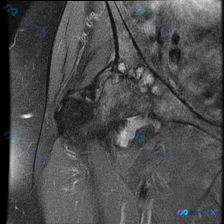

刚整理了一例肘关节MRI冠状位T2加权图像的读片分析,核心问题是观察软组织积液,分享一下完整思路给大家讨论。 病例影像基本信息 提供的是单张肘关节MRI冠状位T2加权图像,核心问题:识别软组织积液相关异常 影像学核心发现 1. 骨骼结构:肱骨远端、尺桡骨近端骨皮质连续,无明显骨折线,骨髓未见明显弥漫...